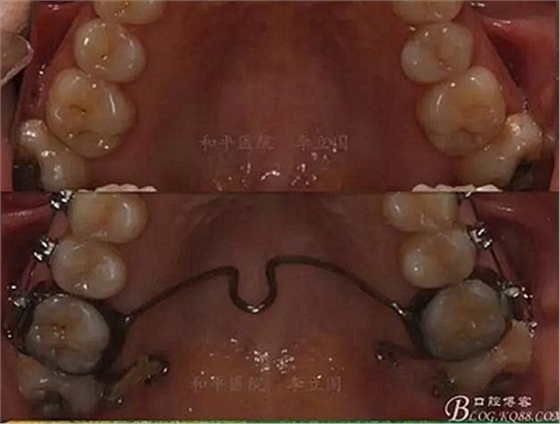

該病例主要為17、27頰側(cè)位同時伴有伸長,當然種植支抗可以解決,但還有簡單實用的辦法嗎?如圖,在橫腭桿遠中延伸出牽引鉤,位置盡量遠離合平面,7粘舌側(cè)扣,牽引力的方向為壓低及舌向,下圖為兩個月的效果,17已到位,27還未到位。